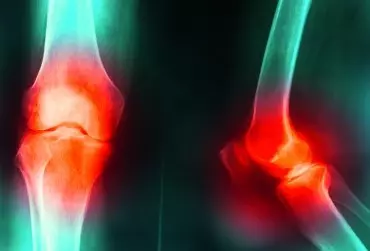

Kolano skoczka - metody lecznicze z punktu widzenia fizjoterapeuty

Obserwowana na przestrzeni lat zwiększona aktywność, zwłaszcza fizyczna, przyczynia się w dużej mierze do powstania różnorodnych urazów i przeciążeń. Jednym z najbardziej narażonych na liczne kontuzje jest narząd ruchu, a w szczególności staw kolanowy.